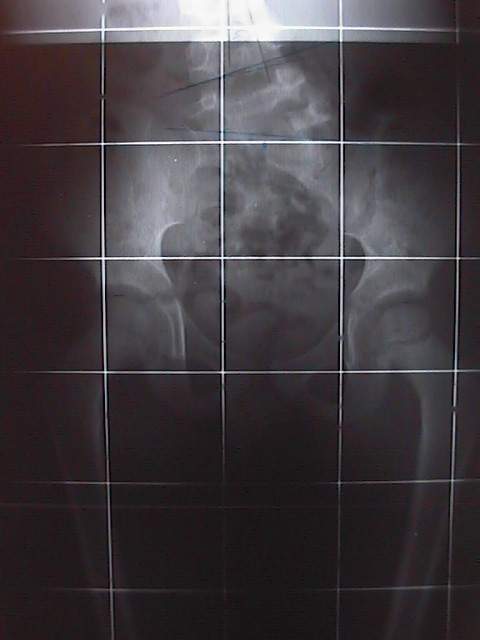

Quand ces anomalies se présentent à un très jeune âge et entraîne une scoliose, il n’y a parfois que la chirurgie qui permet de trouver une solution. Nous vous proposons un cas très particulier d’une hémi-vertèbre droite semi-segmentée L5 fusionnée en S1 avec lyse isthmique et densification des bords L4 gauche chez un enfant de 7 ans : L’histoire de O’Malay (né en 1995)O’Malay, de dos le 13 décembre 2000 La raison pour laquelle la maman de O’Malay amène son fils chez l’ostéopathe, c’est parce qu’il se tient mal ! Dès le déshabillage, le simple fait de mettre O’Malay devant la glace quadrillée montre qu’il y a effectivement un quelque chose d’anormal. La photo est parlante par elle-même. Il est proposé à la maman de faire une radiographie de l’ensemble de la colonne (full spine) et de la région lombaire, face et profil. C’était le 13 décembre 2000. En voici les résultats.Radio de profil : Hémi-vertèbre droite de L5Radio de face de L 5Radio de profil de L 5Radio du bassin de faceRadio de trois quarts : droit & gauche Un scanner est effectué en 2001, dont la technique comporte une acquisition hélicoïdale de 3 mm avec des reconstructions 2 D et 3 D.Scanner avec acquisition hélicoïdale La conclusion est nette : « On retrouve l’hémi-vertèbre droite semi-segmentée L5 fusionnée en S1. II s’y associe une lyse isthmique avec densification des bords L4 gauche (vertèbre sus jacente) ».Scanner avec reconstruction en 3 DDécision chirurgicale Une décision chirurgicale est prise avec comme indication : « résection de l’hémivertébre par doubles voies d’abord pour éviter le déséquilibre progressif qui va s’accentuer petit à petit avec la croissance ». L’intervention chirurgicale se passe très bien. La voie d’abord antérieure est privilégiée avec dissection du muscle psoas droit et résection triangulaire de l’hémi-vertèbre.La voie d’abord postérieur est ensuite réalisée : ablation complète de l’hémi-vertèbre et mise en place d’un matériel avec crochet sur le trou sacré de S2 et sur la lame de L4. Un greffon osseux est mis en place aussi bien en avant qu’en arrière.Un corset de maintien lombaire sera porté pendant 4 mois. La mise debout est progressive. Un contrôle radiologique est effectué pour vérifier la position de la colonne vertébrale, celle du matériel et du greffon.Contrôle radiologique postopératoireMise en route… La mise en position debout ne se fait pas comme prévu : Une sciatalgie droite est diagnostiquée avec « douleurs suspendues au niveau du creux poplité, variable dans sa symptomatologie au cours des journées d’hospitalisation ».La douleur disparaît en position allongée et revient dès la reprise de la marche.Un IRM est pratiqué sans résultat. Le retour à la maison est effectif 10 jours après l’intervention avec une prescription d’antalgiques. Dès le lendemain, les douleurs dans le membre inférieur s’aggravent en position debout au point que la marche est impossible. La maman prend sur elle d’aller revoir l’ostéopathe. En fait, O’Malay souffre d’une psoïte aiguë, avec signe du héron manifeste et une perte complète de confiance dans son membre inférieur droit. Un traitement ostéopathique tissulaire est entrepris au niveau de la cicatrice antérieure, ce qui permet de soulager la douleur de la cuisse.La douleur de type sciatalgie, diagnostiquée à l’hôpital est provoquée par une hyper-contracture des ischio-jambiers qui servent à maintenir l’enfant debout, genou plié.Un ré-apprentissage de la marche se fait progressivement dans la foulée à genoux de manière ludique.Progressivement, O’Malay passe des pleurs au sourire puis, tout à coup, ce sont des éclats de rire. La partie semble gagnée. La maman appelle le lendemain au téléphone pour annoncer triomphalement que son fils est debout et marche normalement.Cette photo a été prise le 14 octobre 2002Chapeau au médecin orthopédiste ! En consultant l’ensemble du dossier de cet enfant, né en 1995, on ne peut que dire « chapeau » au chirurgien orthopédiste qui a pris la responsabilité d’opérer.